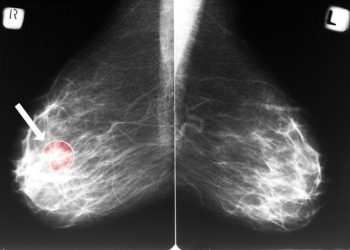

The doctor uses tests to find out how large the cancer is and if it has spread to nearby tissues,...